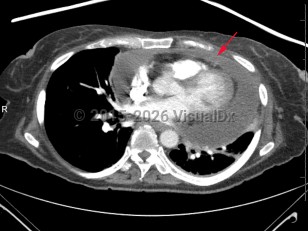

Aortic dissectionAortic dissection

Pericardial effusionPericardial effusion

Cardiac tamponadeCardiac tamponade